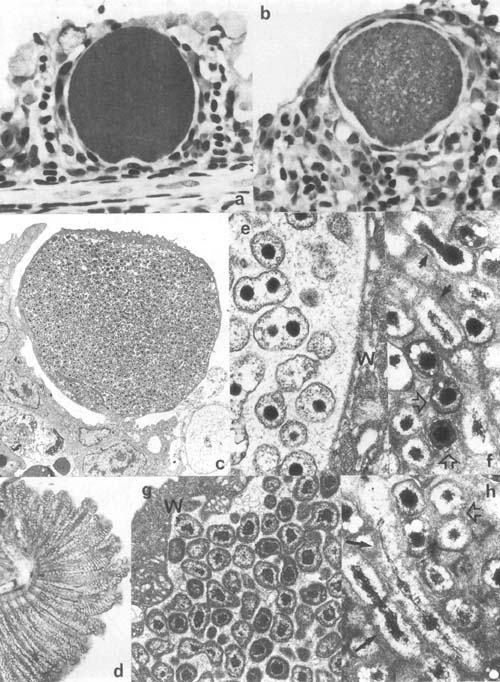

Plate 5. Epitheliocystis: a,b. Hypertrophic epitheliocystis infected cells on gills of Oreochromis aureus, Israel. c. Low mag. transmission electron microscopic (TEM) view of hypertrophic epitheliocystis infected cells (approx. 27 μm in diam) in gills of carp, Israel. d. Hyperinfected gill of Mugil cephalus, Israel. e–h. TEM view of epitheliocystis organisms: e. dividing round bodies (0.7 μm in diam.) and f,h. rods or elongate bodies (1–2 μm long) (same arrows), and cocci (elementary bodies) (0.5 × 0.3 μm) (open arrows) of Oreochromis Epitheliocystis; g, round bodies of carp epitheliocystis (0.4–0.8μm in diam) (W- host cell wall).

Plate 5. Epitheliocystis (legend p. 25)